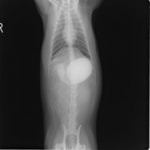

9歳 チワワ 4.8kg

主訴:2日前の夜に桃の種を飲み込んだとのこと。元気・食欲に問題はなく、嘔吐などの消化器症状もみられなかった。誤飲した当日に他院にて催吐処置を試みたが、吐き戻さなかったとのこと。

単純レントゲン検査:明らかな異常所見なし

消化管バリウム造影レントゲン検査:胃内にて異物の存在を疑う異常所見を認めた。

造影直後

内視鏡検査:内視鏡下にて、バスケット鉗子を用いて胃内異物を摘出。

異物内容:桃の種 (約4cm大 写真上)、とうもろこしの芯 (約2.5cm大 写真下)

本症例は、床に落としてしまった桃の種を誤飲していました。動物の体格に対して異物が非常に大きく、開腹手術となる可能性があった症例でした。また、桃の種と一緒に出てきたとうもろこしの芯は、日々のおやつとして与えていたものということでした。とうもろこしの芯は非常に硬く、小さく切って与えても消化されず、長期間胃内に残ってしまうことや腸閉塞の原因となる為、注意が必要です。